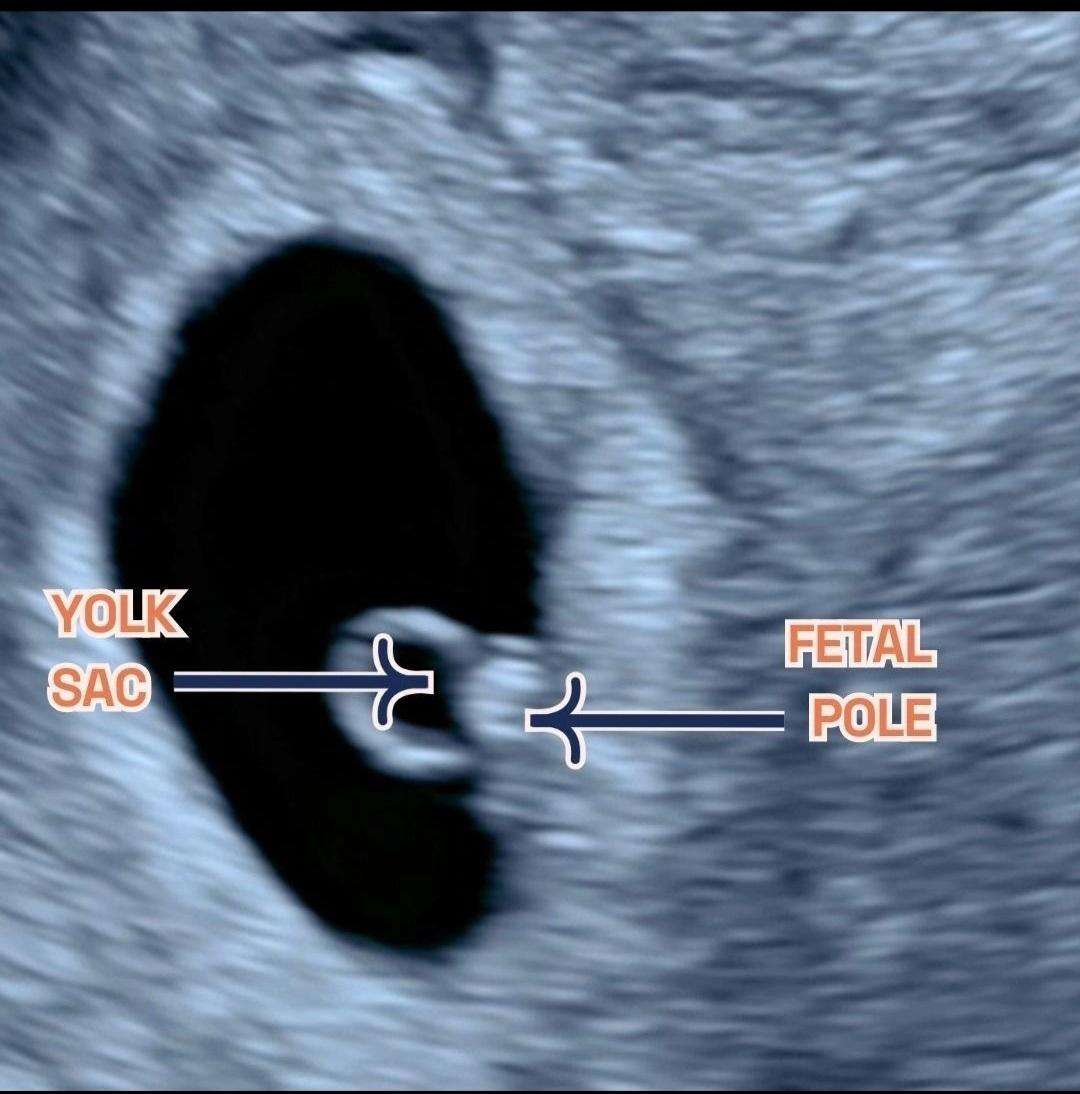

임신 초기에는 주수보다 아기집 크기와 내부 구조가 더 중요하게 판단됩니다. 현재 아기집이 약 8.8mm라면 일반적으로 난황이 보이기 시작하는 경계 구간에 해당합니다. 다만 이 시기에는 배란 지연, 착상 시점 차이로 인해 정상 임신이어도 난황이 아직 보이지 않는 경우가 실제로 적지 않습니다.

의학적으로는 아기집이 10mm 이상인데도 난황이 전혀 보이지 않을 때 비로소 blighted ovum(무배아 임신)을 의심합니다. 지금 수치는 그 기준에 약간 못 미치므로 현 시점에서 유산을 단정하는 것은 이릅니다. 예후가 좋지 않다고 단정할 단계도 아닙니다.

• 아기집이 8-10mm 이상이라면 대부분 난황이 관찰되기 시작하여야 하는데 그것이 관찰되지 않는다면 우려스러운 부분이라고 볼 수 있습니다. 다만 임신 극초기이기 때문에 안 보이는 것일 수도 있기 때문에 다음주에도 추적관찰을 하자고 이야기 하는 상황일 것으로 사료됩니다. 너무 추적관찰 간격을 짧게 잡는 것도 크게 의미는 없기 때문에 권유받은대로 다음주에 보시는 것이 좋겠습니다.